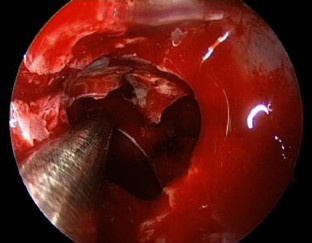

Fig. 4